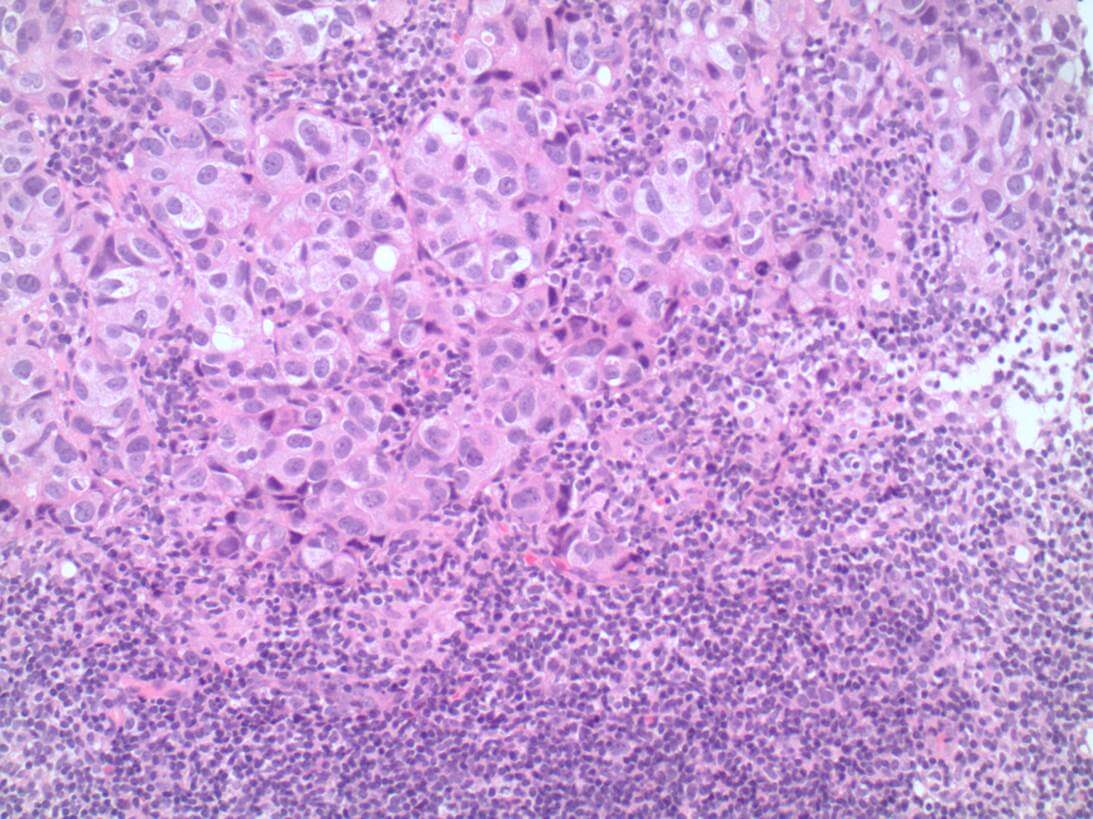

Invasive carcinoma is most commonly ductal carcinoma of no special type, with invasive lobular carcinoma the next most common. Invasive lobular carcinoma may show more extensive disease than appreciated clinically, or on imaging pre-operatively, and it is useful for this identification to assist with planning surgery. Tumour grade is a measure of tumour differentiation and is an important prognostic variable that influences decisions about additional treatment such as chemotherapy. Grading takes into account the ability of the tumour to make glands, the degree of nuclear pleomorphism and the proliferative rate measured by counting mitoses (Figure 1 – grade 1 invasive carcinoma, Figure 2 – grade 3 invasive carcinoma).

Figure 2: Grade 3 invasive carcinoma

This image depicts grade 3 invasive carcinoma. Professional medical imaging for clinical reference and educational purposes. [umbracoNodeId=9798]